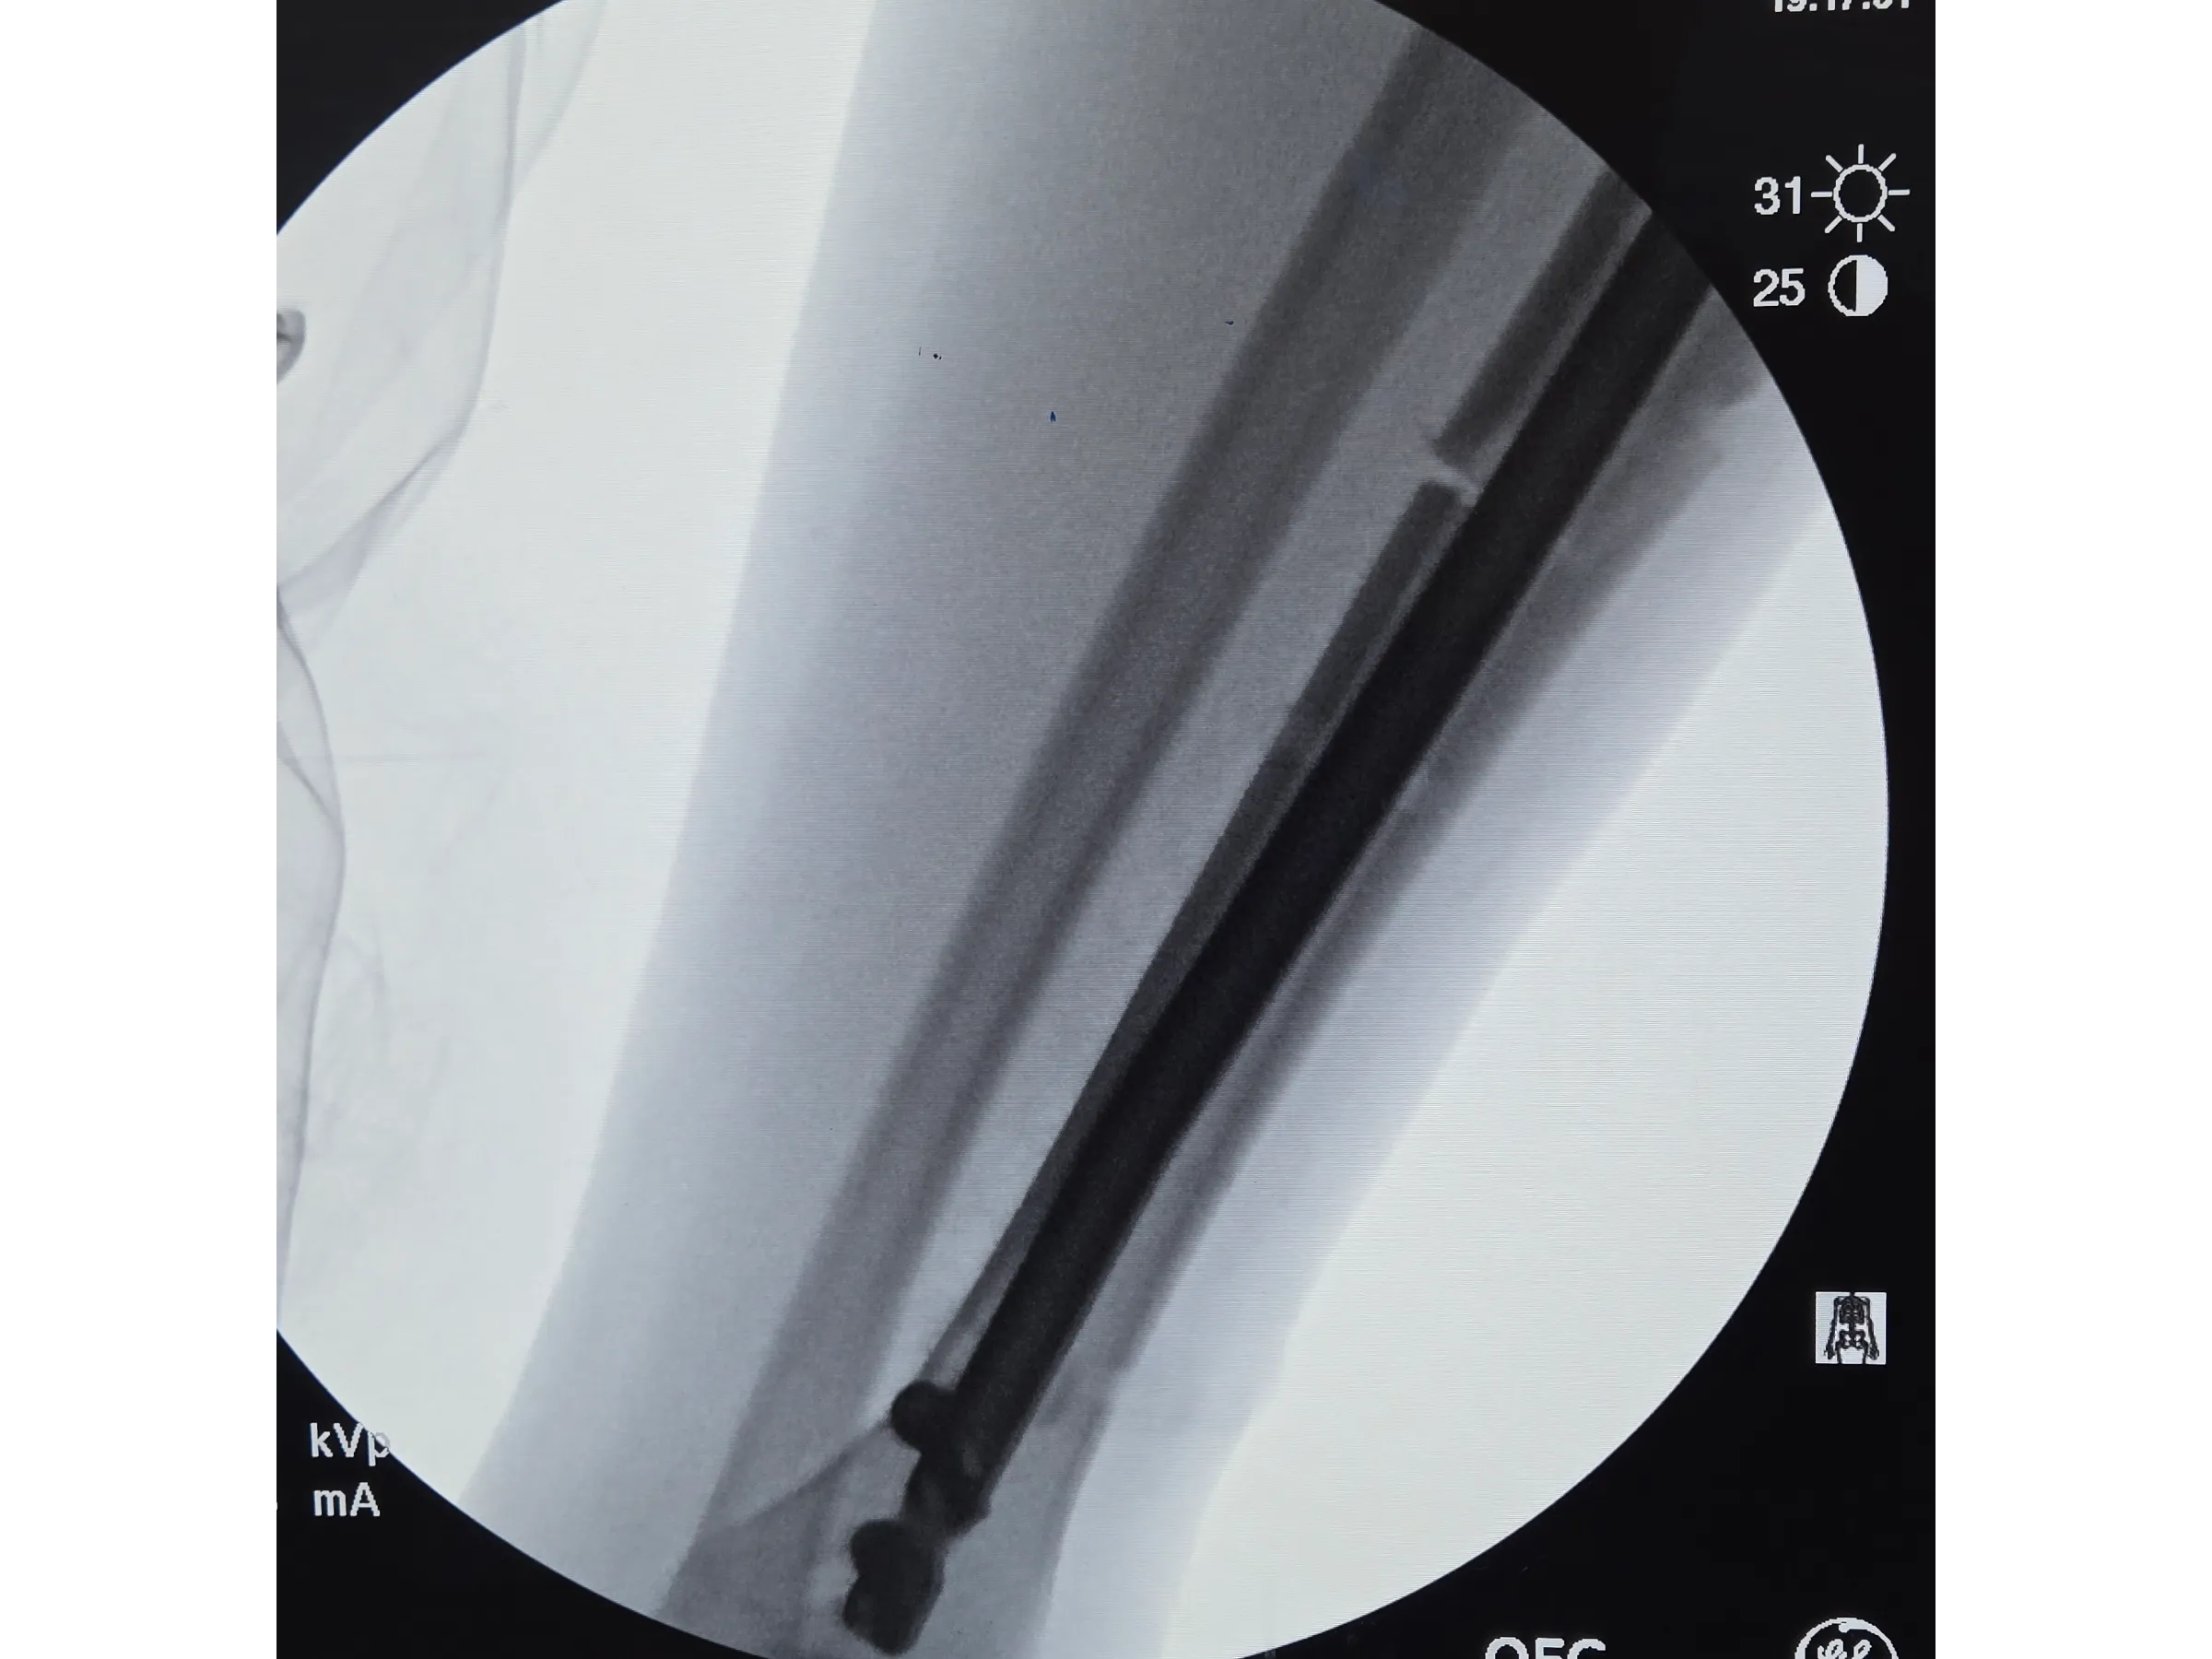

A estabilização de fraturas diafisárias da tíbia exige precisão no portal de entrada, alinhamento axial e proteção das partes moles. Este treinamento apresenta, de forma objetiva e prática, a técnica de implantação de haste intramedular por via infrapatelar, com demonstração detalhada dos passos cirúrgicos, controle radiográfico e execução minimamente invasiva sob perspectiva técnica.

- Bloqueios proximais e distais com abordagem minimamente invasiva;

- Bloqueios Proximais e Distais Minimamente Invasivos: Execução de bloqueios cruzados e distais com pequenos portais e controle por intensificador;

- Avaliação Pós-Implante: Critérios para confirmar estabilidade, alinhamento e ausência de proeminência da haste.